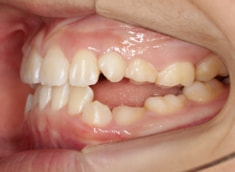

治療後(1年5ヶ月後)

治療開始から11ヶ月